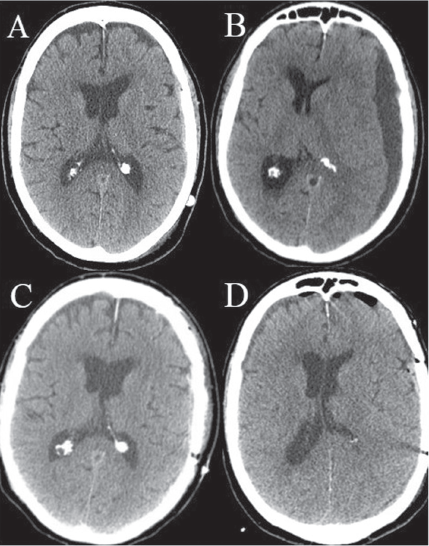

encephalopathy

Emily Ann K. Andaya, MD; Nabil Rizk, MD; Sumit Folga, MD

A 51-year-old white male with mental disability and known seizure disorder presented to his neurologist with a new onset of headache, dizziness, confusion, weakness, lethargy, and hand tremors.